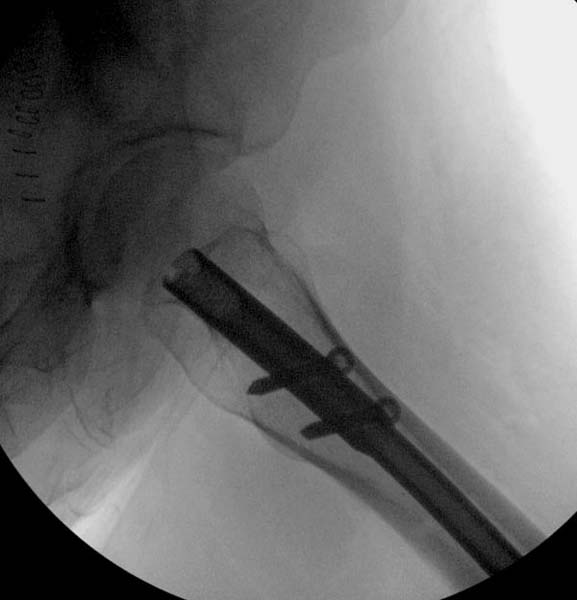

Закрытый БИОС решает множественные проблемы связанные с лечением переломов, но проблема дистальной блокировки без рентгена до сих пор остается нерешенной. Рекламированные производителями приспособления для дистальной блокировки из-за различной кривизны кости не эффективны или стоит очень дорого (Smith&Nephew SureLock). Задержка операции из-за блокировки не всегда удовлетворяет, и многих вынуждает искать альтернативные методы фиксации. С результатами таких действий, остеомиелитом и несращениями, встречаемся в ежедневной жизни..

Для решения проблемы дистальной блокировки компания DigiMed недавно предложила систему блокировки без рентгена. Пока в стране только два набора и только для антеградных гвоздей, но компания работает над созданием устроиства для других гвоздей тоже..

Результат первых случаев показала отсутствие разницы между занятиями на муляжах, а также Workshop и с удивительной точностью вывел латерально над кожей специальное сверло. Дальше по сверлу тонкий направитель и проводится сверление каннюлированным сверлом....